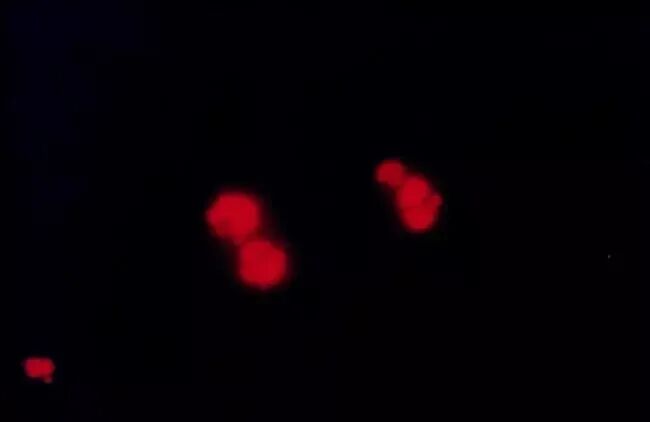

| 衰老的HUVEC

Propidium iodide(PI碘化丙啶)是一種核酸染料,常用于細(xì)胞凋亡(apoptosis)或細(xì)胞壞死(necrosis)的檢測(cè)和流式細(xì)胞儀分析。PI不能通過(guò)正常完整的細(xì)胞膜,故細(xì)胞在處于壞死或晚期凋亡時(shí)細(xì)胞膜被破壞,這時(shí)可為PI著紅色,可以用來(lái)分辨壞死細(xì)胞/正常細(xì)胞。

2. 加入另一種可以透過(guò)細(xì)胞膜的核酸染料,就可以通過(guò)兩種染料將活細(xì)胞和死細(xì)胞區(qū)分開(kāi)。PI經(jīng)常被用來(lái)與Calcein-AM或者FDA等熒光探針一起使用,能同時(shí)對(duì)活細(xì)胞和死細(xì)胞染色。PI-DNA復(fù)合物的激發(fā)和發(fā)射波長(zhǎng)分別為535 nm和615 nm。